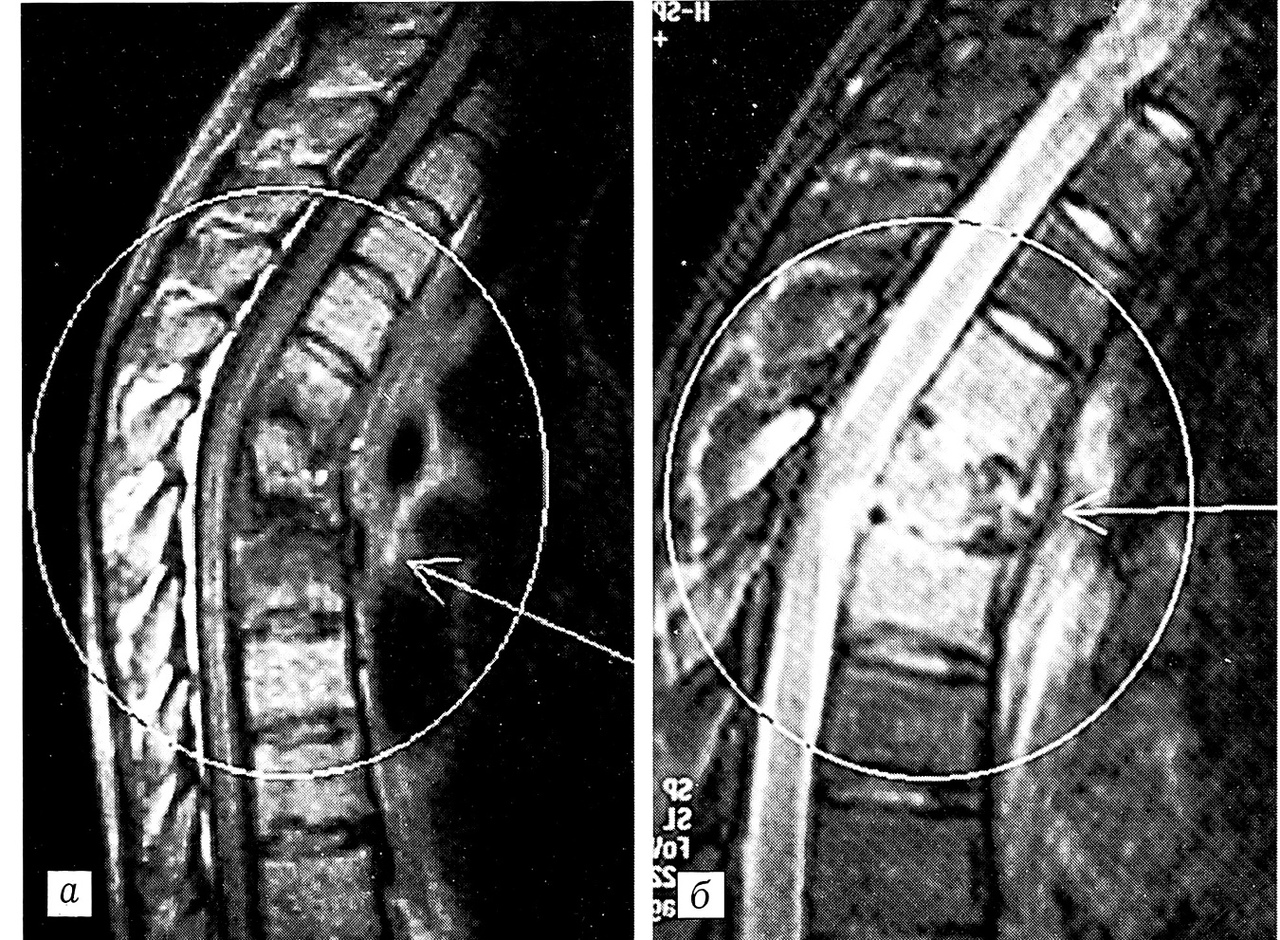

Рис. 1. МРТ больного К. a — до лечения: остеомиелит L5-S1 позвонков с пресакральным абсцессом; б — через 1,5 года после консервативного лечения: спонтанный блок на уровне L5-S1 позвонков.

Больной К., 44 лет, поступил в клинику 12. 01.99 с жалобами на выраженные боли в пояснично-крестцовом отделе позвоночника, усиливающиеся при движениях и иррадиирующие при кашле в нижние конечности, повышение температуры тела. Заболел остро 22.12.98: появились озноб, боли в позвоночнике, температура тела повысилась до 39°С. Лечился у терапевта с диагнозом «пневмония». Несмотря на проведенное антибактериальное лечение, состояние больного ухудшилось, и 6.01.99 он был госпитализирован в инфекционную больницу, откуда переведен в клинику травматологии и ортопедии. При поступлении состояние больного средней тяжести. Положение вынужденное — на спине. Движения в поясничном отделе позвоночника ограничены, болезненны при поворотах туловища, поясничный лордоз сглажен. При перкуссии боль в проекции остистых отростков L4, 1_5 и S1 позвонков. Нагрузка по оси позвоночника безболезненна. Мышцы поясничного отдела напряжены. Движения в тазобедренных суставах ограничены, болезненны. Расстройств чувствительности нет. Патологических неврологических симптомов не выявлено. Анализ крови: СОЭ 60 мм/ч, л. 11,8-109/л, эр. 3,0-0,2л, НЬ 93 г/л, п. 3%, с. 77%. На рентгенограммах пояснично-крестцового отдела позвоночника: умеренные дистрофические изменения в телах L5 и S1. Остеохондроз диска L5-S1. МРТ (рис. 1, а): признаки дисцита L5-S1 (вещество диска резко отечно), умеренная отечность тел L5 и S1; визуализируется пресакральное скопление высокобелковой жидкости(абсцесс?) преимущественно на уровне S1.

Проведено консервативное лечение: клафоран по 1 г 4 раза в сутки внутриаортально через катетер, введенный в бедренную артерию до уровня L2 позвонка; гентамицин по 80 мг 2 раза в сутки внутривенно. Применялась дезинтоксикационная, иммунокорригирующая, витаминотерапия. Гепарин 2500 ЕД внутривенно, УФО крови и инкубация клеточной массы. Состояние больного улучшилось — уменьшился болевой синдром, нормализовалась температура тела. Общий анализ крови: СОЭ 43 мм/ч, л. 7,2 -109/л, НЬ 120 г/л. Выписан в удовлетворительном состоянии. Обследован через 1,5 года. Жалоб нет. На МРТ — спонтанный блок на уровне L5-S1 позвонков (рис. 1, б). Анализы крови нормальные.

Ортопедический статус: ходит с трудом, отмечает резкие боли в грудном отделе позвоночника. Пальпация и перкуссия остистых отростков ТЗ-5 позвонков резко болезненна, определяется кифотическая деформация. Положительный симптом Томпсона. Неврологический статус: брюшные рефлексы отсутствуют, коленные и ахилловы рефлексы оживлены, нижний парапарез. Анализ крови: НЬ 100 г/л, л. 17,9* 109л, СОЭ 34 мм/ч. МРТ (рис. 3, а): позвонок Тб полностью разрушен, клиновидно деформирован. Замыкательные пластинки разрушены. Внутренняя структура гиперинтенсивна (отек костного мозга). Определяется эпидуральный абсцесс на уровне Т5-6 позвонков с четкими признаками компрессии спинного мозга. Имеются признаки превертебрального абсцесса. На аксиальных срезах картина воспалительного поражения Т4-6 позвонков с деструкцией Т5, эпидуральный абсцесс с компрессией спинного мозга, паравертебральным абсцедированием (вероятнее всего, остеомиелит).

Послеоперационный период без осложнений. Больная выписана в удовлетворительном состоянии в ортопедическом корсете через 1 мес после операции. Обследована через 2 года: жалоб нет, температура тела нормальная, анализы крови в пределах нормы, регресс неврологической симптоматики. Является инвалидом II группы. По данным МРТ — костный блок на уровне Т4-6 позвонков (рис. 3, б).

Рис. 3. МРТ больной И. a — до операции: деструкция тел Т4~6 позвонков, превертебральный абсцесс; б — через 2 года после операции: костный блок Т4-6 позвонков.